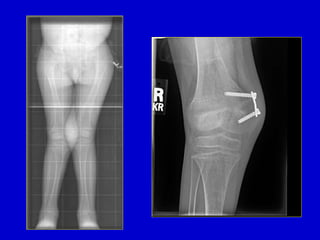

Surgical Correction: Proximal Tibial

Osteotomy

• Demonstration of opening

wedge tibial osteotomy

procedure for correction

of infantile blount’s

disease

• Usually recommend slight

overcorrection into mild

valgus (reverse excessive

compression forces

medially: avoid injury to

physis)